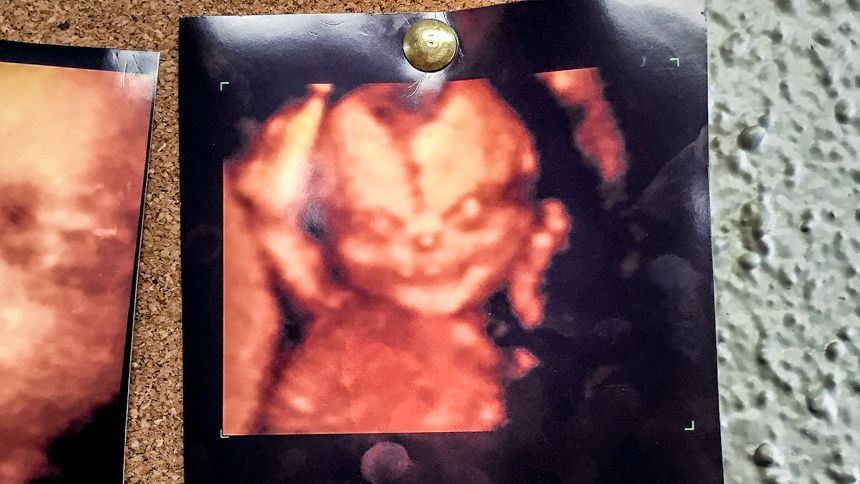

A man who went to the doctor with his pregnant wife said that the couple decided against a detailed ultrasound after seeing another parent who had the image of a "demon" in their ultrasound.

In a post on the website Reddit late last week, a user shared a photo of an ultrasound that was posted outside of his doctor's office.

"Wife and I went to get a '4D' ultrasound of our unborn child," the man wrote. "Saw this picture. Changed our minds."

The photo contained an image of a fetus whose appearance was described by Redditors as a "demon."

"The 4th D is for demon," one person wrote.